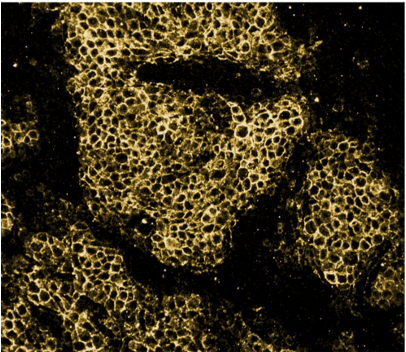

Nedanstående bilder visar vävnadsprover inmärkta av Lumitos reagenser och scannade i Lumitos produkt, som i framtiden erbjuder nya möjligheter att koppla beslutsstöd i form av AI. Bildkvaliteten har förbättrats genom förfinad optik och scannerns hastighet har ökat.

Den vänstra bilden visar en standardininfärgning. Denna typ av bild studerar patologerna idag när de söker efter cancer i bröstvävnad. Den högra bilden (som är samma vävnadssnitt som den vänstra bilden) visar Lumitos UCNP-inmärkning, Her-2. I denna inmärkning är både bakgrundssignal och autofluorescens eliminerade och resultatet blir en tydligare bild som visar förekomst av cancer – ju mer gult desto större förekomst.